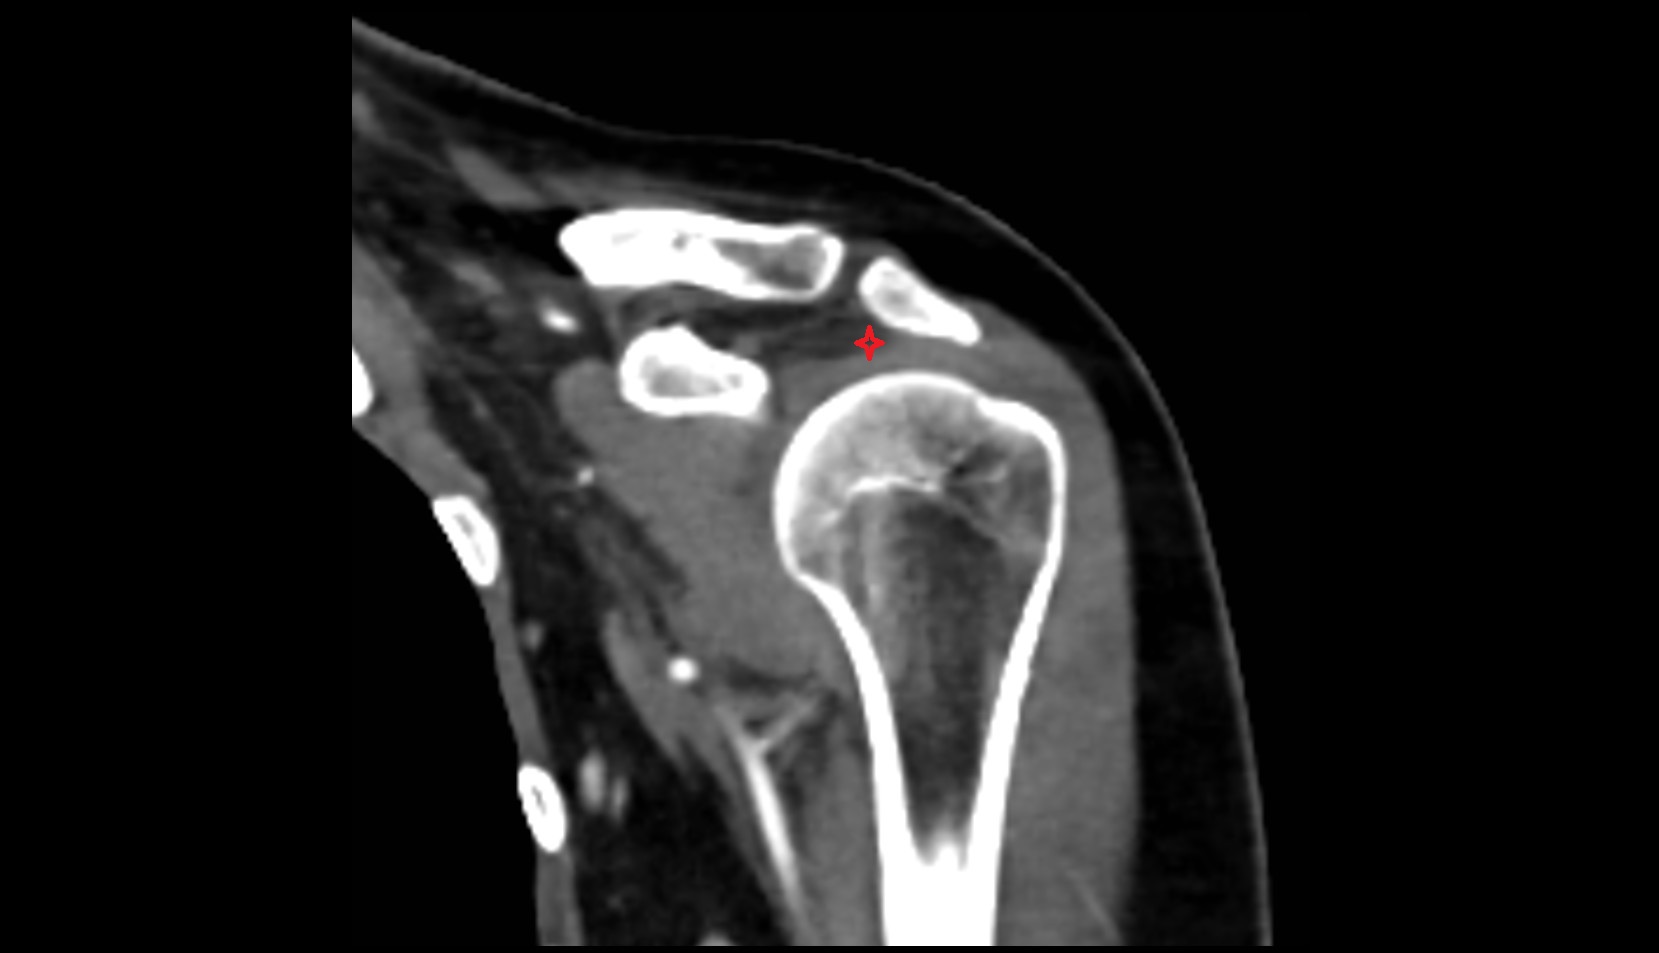

- Subacromial space